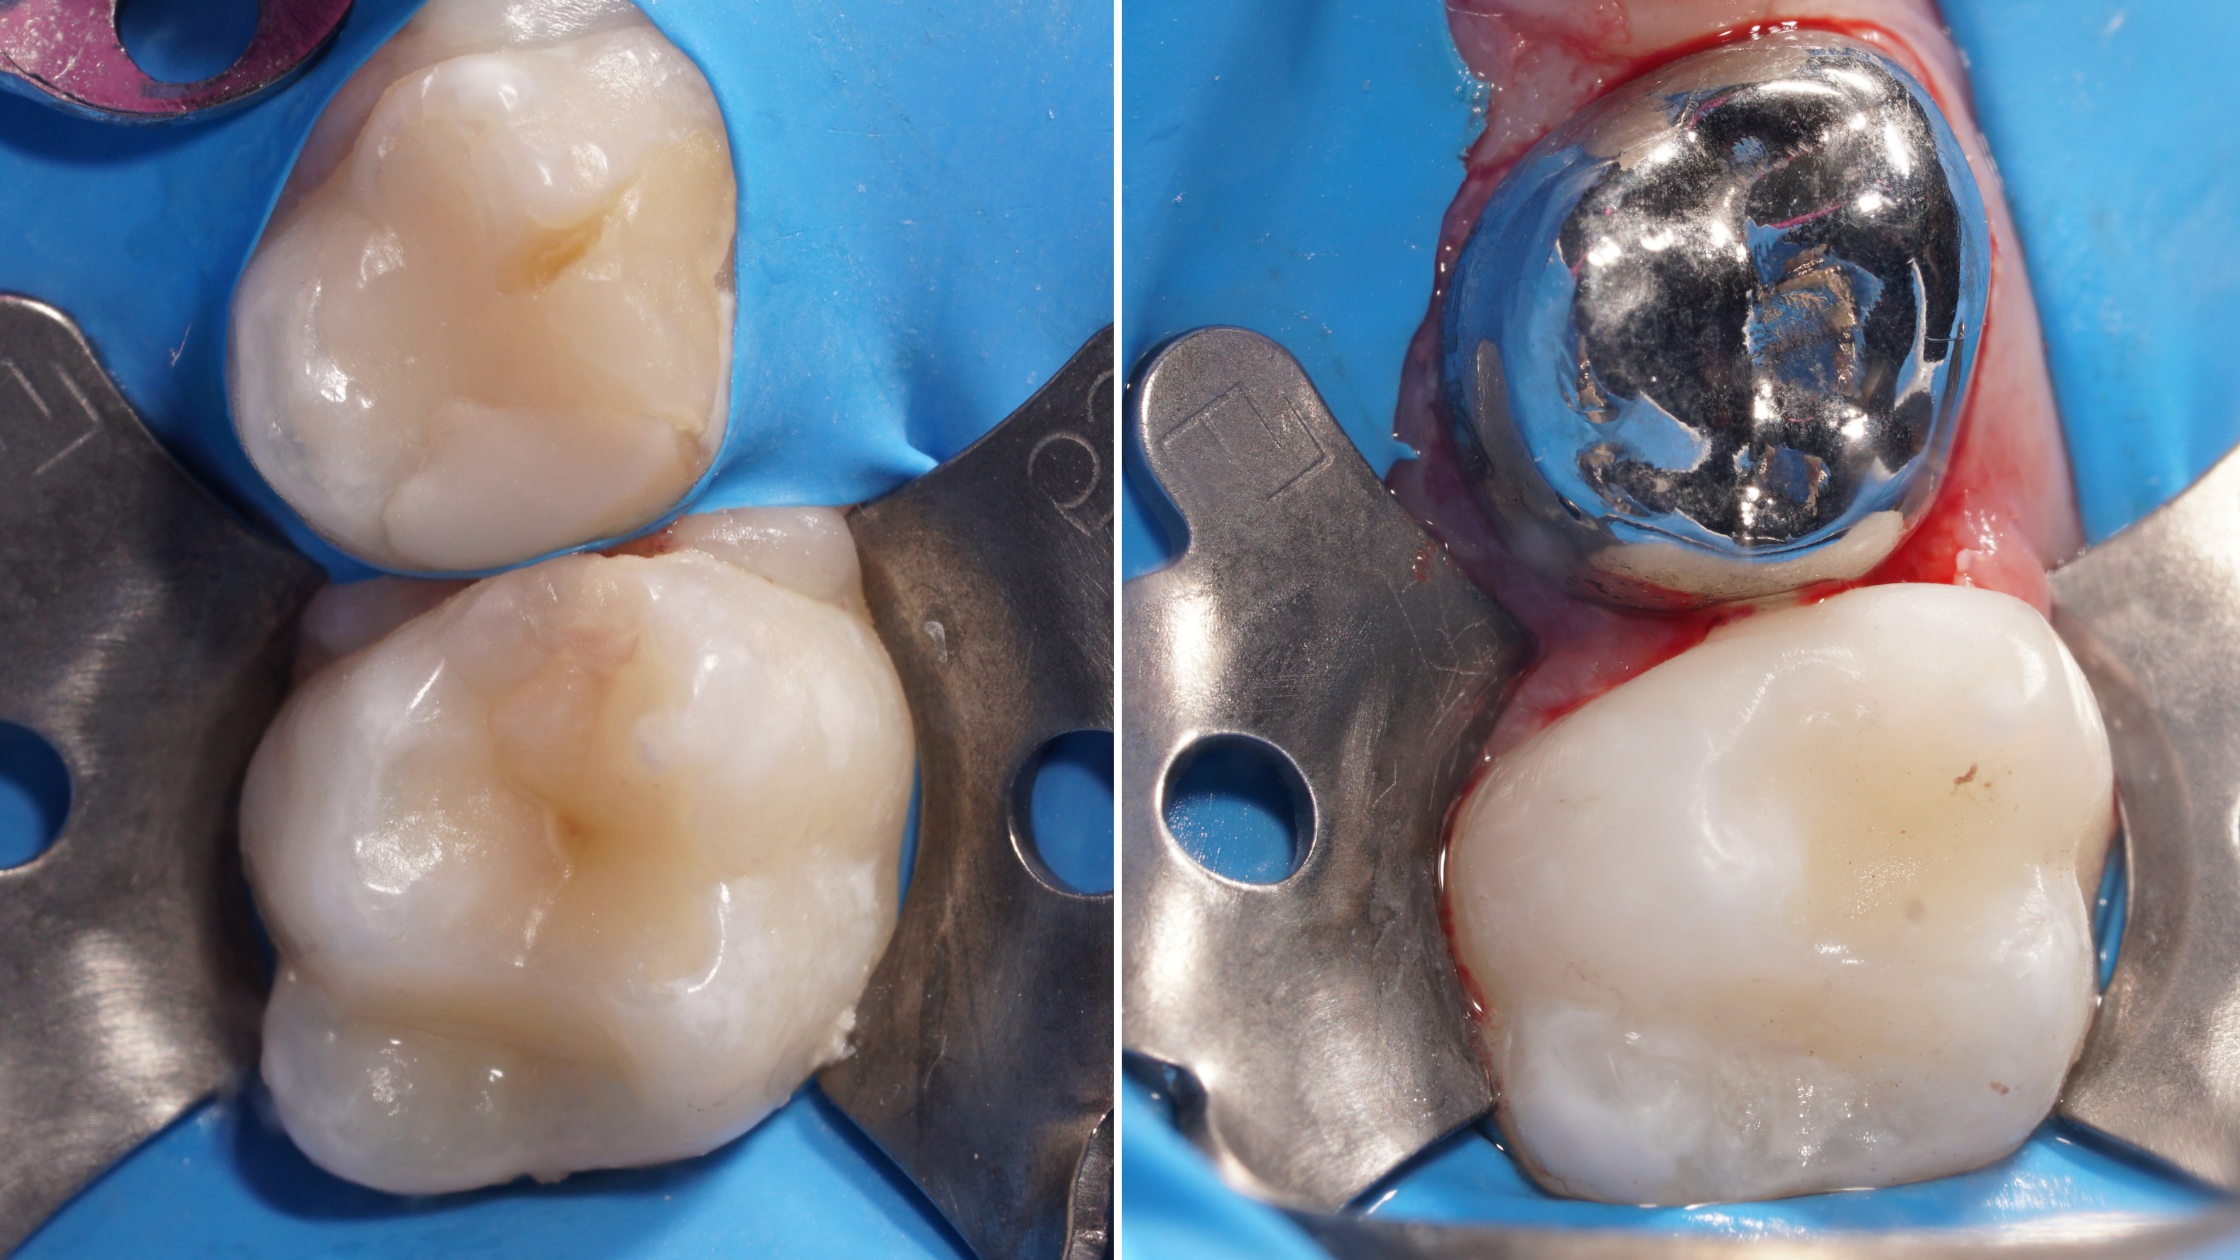

Izolacja i odbudowa klasy II

• zakładanie koferdamu na zęby mleczne i pierwsze trzonowce

• preparacja ubytku klasy II - specyfika zębów mlecznych

• praca z matrycami, kontrola punktów stycznych, uzyskanie szczelności brzeżnej

• wykończenie i ocena jakości wypełnienia

Szlifowanie zębów mlecznych pod korony

• założenie korony stalowej - technika Hall

• szlifowanie 2-3 zębów mlecznych pod korony stalowe

• dobór rozmiaru korony, przymiarka

• cementowanie koron stalowych